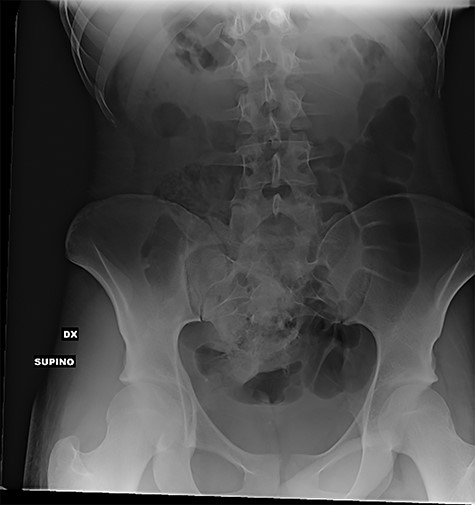

The subsequent abdominal X-rays demonstrated the complete absence of further foreign bodies (Fig. 3).

Supine abdominal X-rays (frontal view): absence of pelvic radiopaque foreign bodies at the end of the procedure